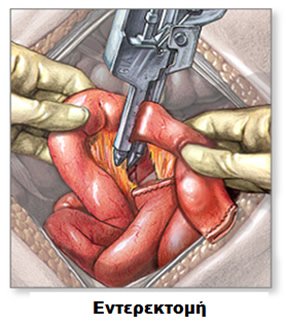

Είτε γίνει «ανοικτά» είτε λαπαροσκοπικά, η χειρουργική επέμβαση κοιλίας πραγματοποιείται για να αντιμετωπίσει το πάσχον τμήμα του εντέρου. Συνήθως, η προβληματική περιοχή εμφανίζει διάτρηση, απόφραξη ή συρίγγιο. Οι δύο πιο κοινές χειρουργικές επεμβάσεις για τη νόσο Crohn είναι η αφαίρεση του τέλους του λεπτού εντέρου και της αρχής του παχέος εντέρου, επέμβαση που ονομάζεται ειλεοτυφλεκτομή, καθώς και η αντιμετώπιση της στένωσης του εντέρου που προκαλεί την απόφραξη, με επεμβάσεις που ονομάζονται εντερεκτομές ή στενωσοπλαστικές. Σε κάθε περίπτωση σκοπός της επέμβασης είναι η διατήρηση όσο το δυνατόν μεγαλύτερου μήκους εντέρου, ώστε να παραμείνει όσο πιο φυσιολογική γίνεται η λειτουργία του πεπτικού σωλήνα που απομένει.